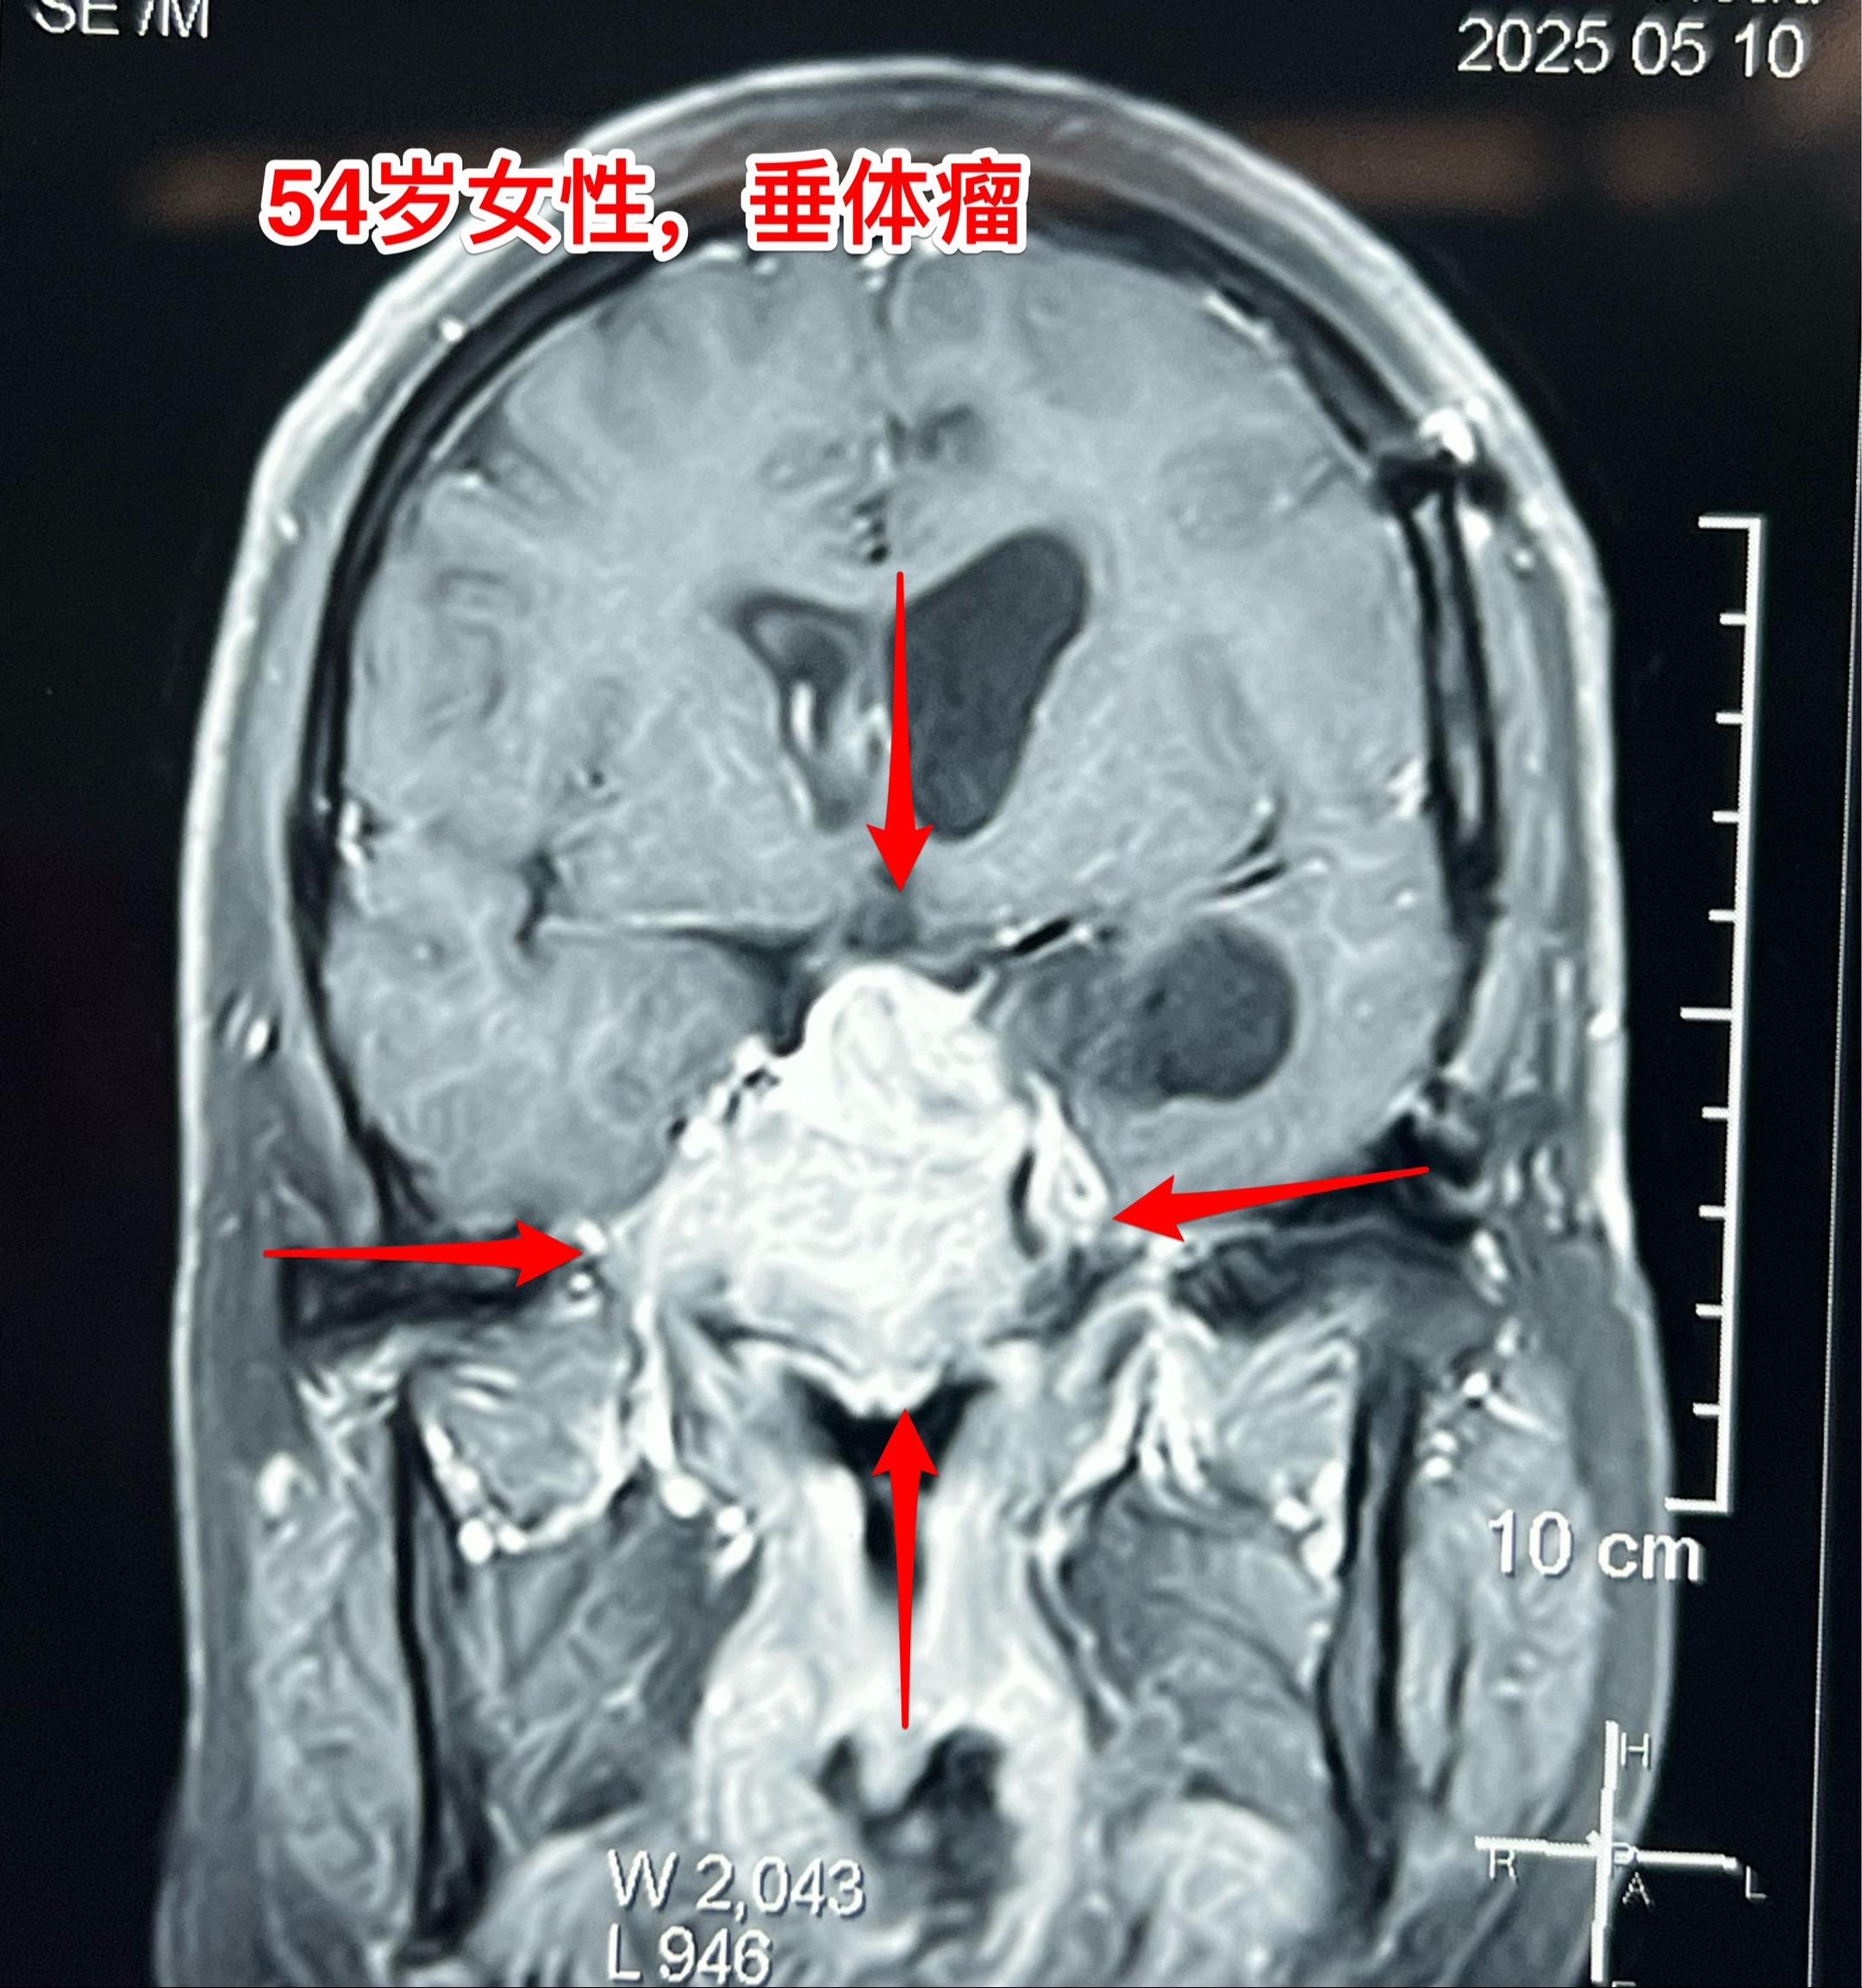

侵袭性垂体瘤第二次手术。54岁女性,2023年9月因垂体瘤作了第一次手术,是开颅手术,当时左眼视力下降。把颅内的肿瘤切除了,蝶窦内、海绵窦内的肿瘤没有动,计划二期手术。 2025年5月病人感觉左眼视力又有下降,来作第二次手术,磁共振、CT显示肿瘤巨大,是典型的侵袭性垂体瘤。这次只能采用经鼻手术了。昨天顺利完成手术。 今天病人没有出现脑脊液鼻漏症状,自感很轻松,精神好。